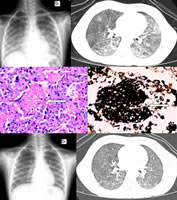

患儿女,7岁,急性淋巴细胞白血病(急淋)完全缓解11个月,气促24天。X线胸片:两肺透光度对称性减低,基底部和肺门周围见少量网结和片絮影,肺尖及肋膈窦未受累(图1)。胸部CT:两肺弥漫磨玻璃样密度影,肺纹理增多,并可见双侧不均匀斑片影(图2)。肺部活检:肺泡间隔增宽,散在淋巴、浆细胞、中性白细胞浸润,部分肺泡腔扩张,内见多量粉染的泡沫样物及红细胞(图3)。六胺银染色(+)(图4),PAS染色(-),抗酸染色(-)。磺胺甲 唑治疗后两周病变明显吸收(图5,图6)。诊断:卡氏肺孢子虫肺炎(PCP)。

X线胸部平片是诊断评估PCP的首选方法。典型胸部X线表现为双肺间质性和(或)肺泡性病变,双肺弥漫性、对称性细小结节和网条影像为主,病灶可迅速扩大、融合,甚至形成白肺。病变呈中心性分布,肺尖与肋膈窦常不受累,似肺水肿。胸部CT特征性表现为弥漫性气腔病变,两肺弥漫或局限磨玻璃样密度改变及间质纹理增多。

病理学肺病变常较弥漫,组织学见肺泡间隔水肿,淋巴细胞、浆细胞浸润,肺泡Ⅱ型上皮增生肥大 ......